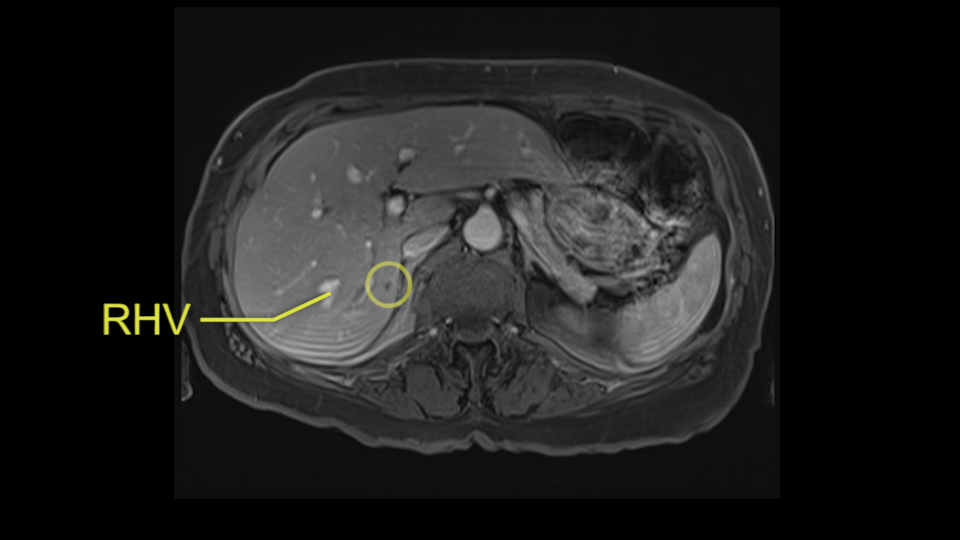

The procedure-specific slowing down moments from a technical point of view for a right hemihepatectomy include a careful evaluation of the inflow structures including the right hepatic artery, the right portal vein, as well to make sure that I have identified and preserved the left hepatic artery and the left portal vein at all times, and minimize any injury or dissection of the common bile duct. Also, I am careful when I mobilize the right liver, not to tear the right triangular ligament and cause bleeding of the liver as I mobilize it off the retroperitoneum and the bare area. In addition, the last procedure-specific slowing down moment is to carefully identify the right hepatic vein and ensure that I encircle it safely without damaging the IVC or the middle and left hepatic vein structures at all times.

So I would then focus on the hepatic outflow because that’s the way we do the operation is by mobilizing the liver. So the vena cava looks quite normal. The right hepatic vein looks quite normal. There are no large additional outflow veins from the right lobe which would generate slowing down moments. The hepatic artery is unremarkable and is not usually an issue we can define the anatomy quite clearly at surgery.

So we’re going through the liver segments now. Here we’ve got the inflow; here’s the main portal vein, right anterior sectoral portal vein, right posterior sectoral portal vein there. Here’s the main here going to the left lobe first of all. So that’s 3 and 2 there, they look clear, and there’s a good size of the left lobe with a good girth. So 3 and 2 look clear. There are usually more feedback branches from the left portal vein to segment 4b but that also looks relatively clear. There’s a little more disease over on the right side there. So that would be...right hepatic vein here...that’s Segment 7. So we’ve got disease in 7, 5, probably in 6 on the right side; at least 3 lesions. That’s the distribution of the lesions.![[Ant. RPV] [Main PV] [Post. RPV]](jpg/preop_as_p5.jpg)